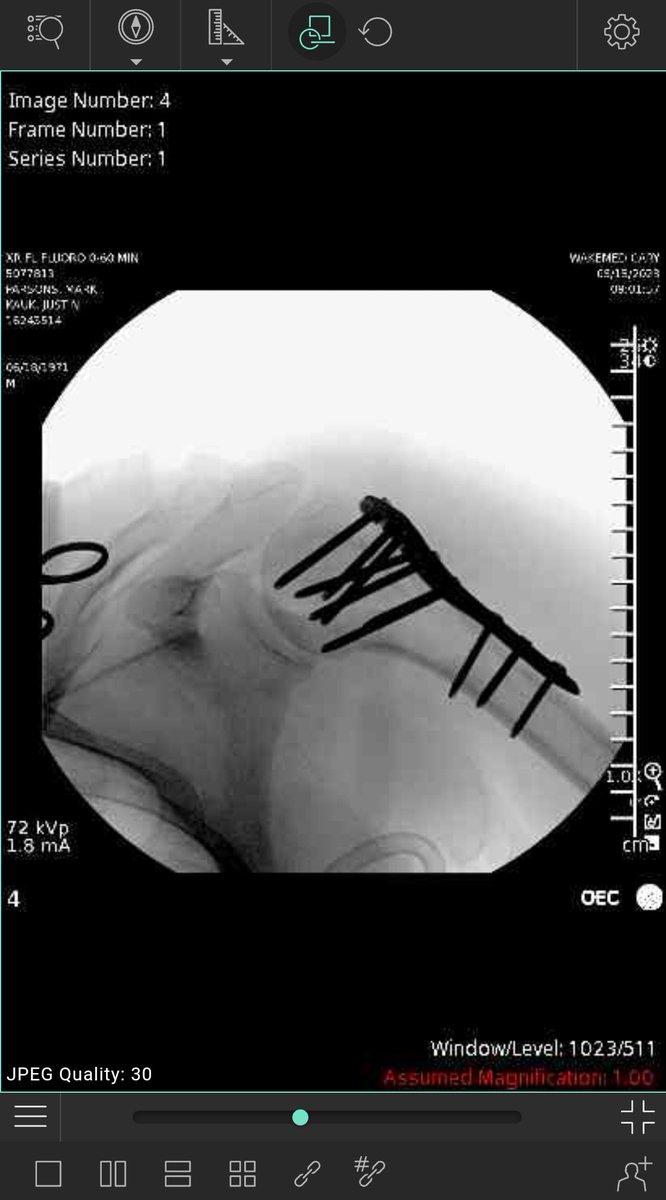

Hey everyone I need your help. I took a nasty fall while running. Broke my arm, needed surgery, 10 screws & a plate. The bills are pretty extensive. If you can help in any way even by boosting this, sharing the link far & wide, be very grateful. gofundme.com/f/gravity-is-a… #retweet